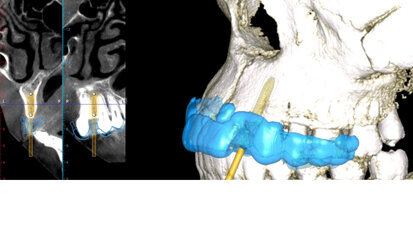

Nový úsměv za jeden den

Čt. 28. května 2020